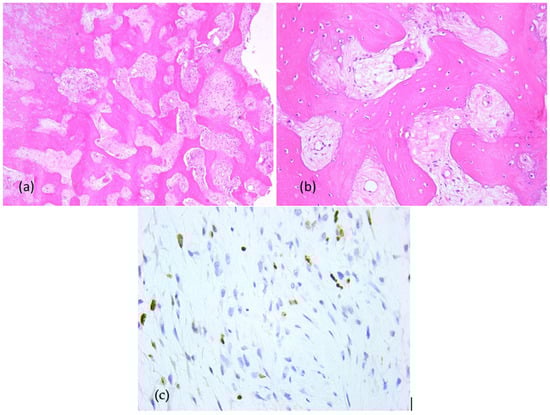

2.3. First Histopathologic Examination